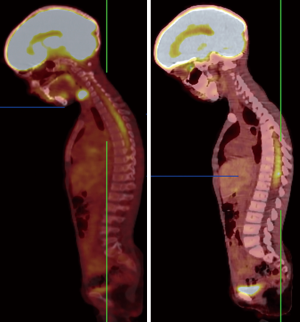

Somatostatin is a neuropeptide released by endocrine cells, neurons, and immune cells which its functions include neuroregulation (sensory, motor, and cognition) and cell growth inhibition by paracrine and autocrine pathways (37,38). Somatostatin works through a group of transmembrane G protein-coupled receptors that enter the cell following binding to specific ligands (39). So far, six subtypes of somatostatin receptors (SSTRs) are discovered including SSTR 1, 2A, 2B, 3, 4, and 5. A broad spectrum of brain tumors express different subtypes of SSTR on their surface including frequent primary brain tumors e.g., gliomas and meningiomas, pediatric brain tumors (medulloblastomas), pituitary adenomas, and supratentorial primitive neuroendocrine tumors (PNETs) (40-43). Dutour and colleague (44) have shown that gliomas and meningiomas, as the first and second most common primary brain tumors, are positive for different subtypes of SSTR. It was demonstrated that although all of them have at least one SSTR subtype, many of these harboring multiple SSTR subtypes. They provided proofs on detecting SSTRs in both tumors and their surrounding tissues, particularly blood vessels. Concerning gliomas, low-grade gliomas (WHO grade I, II) depicted higher expression levels compared to high-grade gliomas (WHO grade III, IV) (45). To date, three 68Ga-DOTA peptides are developed for clinical imaging comprised of 68Ga-DOTA-TOC, 68Ga-DOTA-NOC, and 68Ga-DOTA-TATE. The shared property of these 68Ga-DOTA peptides is the ability in binding to SSTR2, and they differ with regard to their SSTR subtype affinity and profile (Figures 4,5).